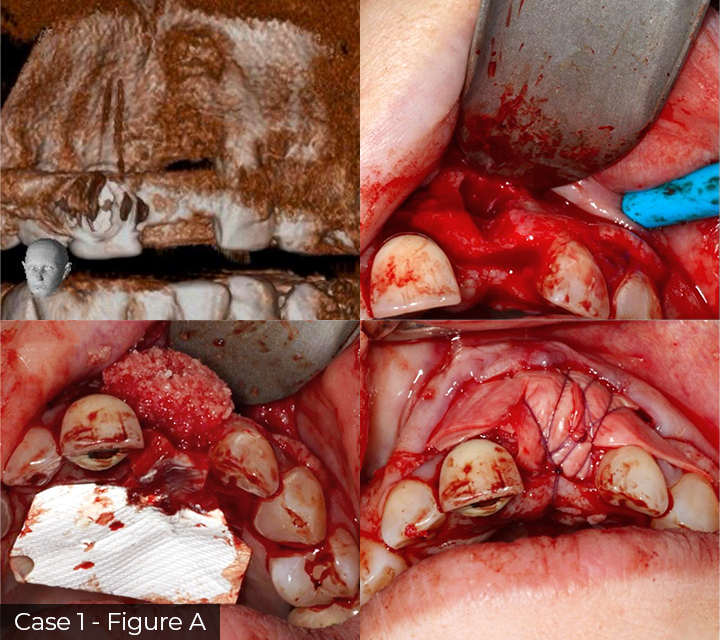

Director’s Clinical Cases

Director’s Clinical Cases